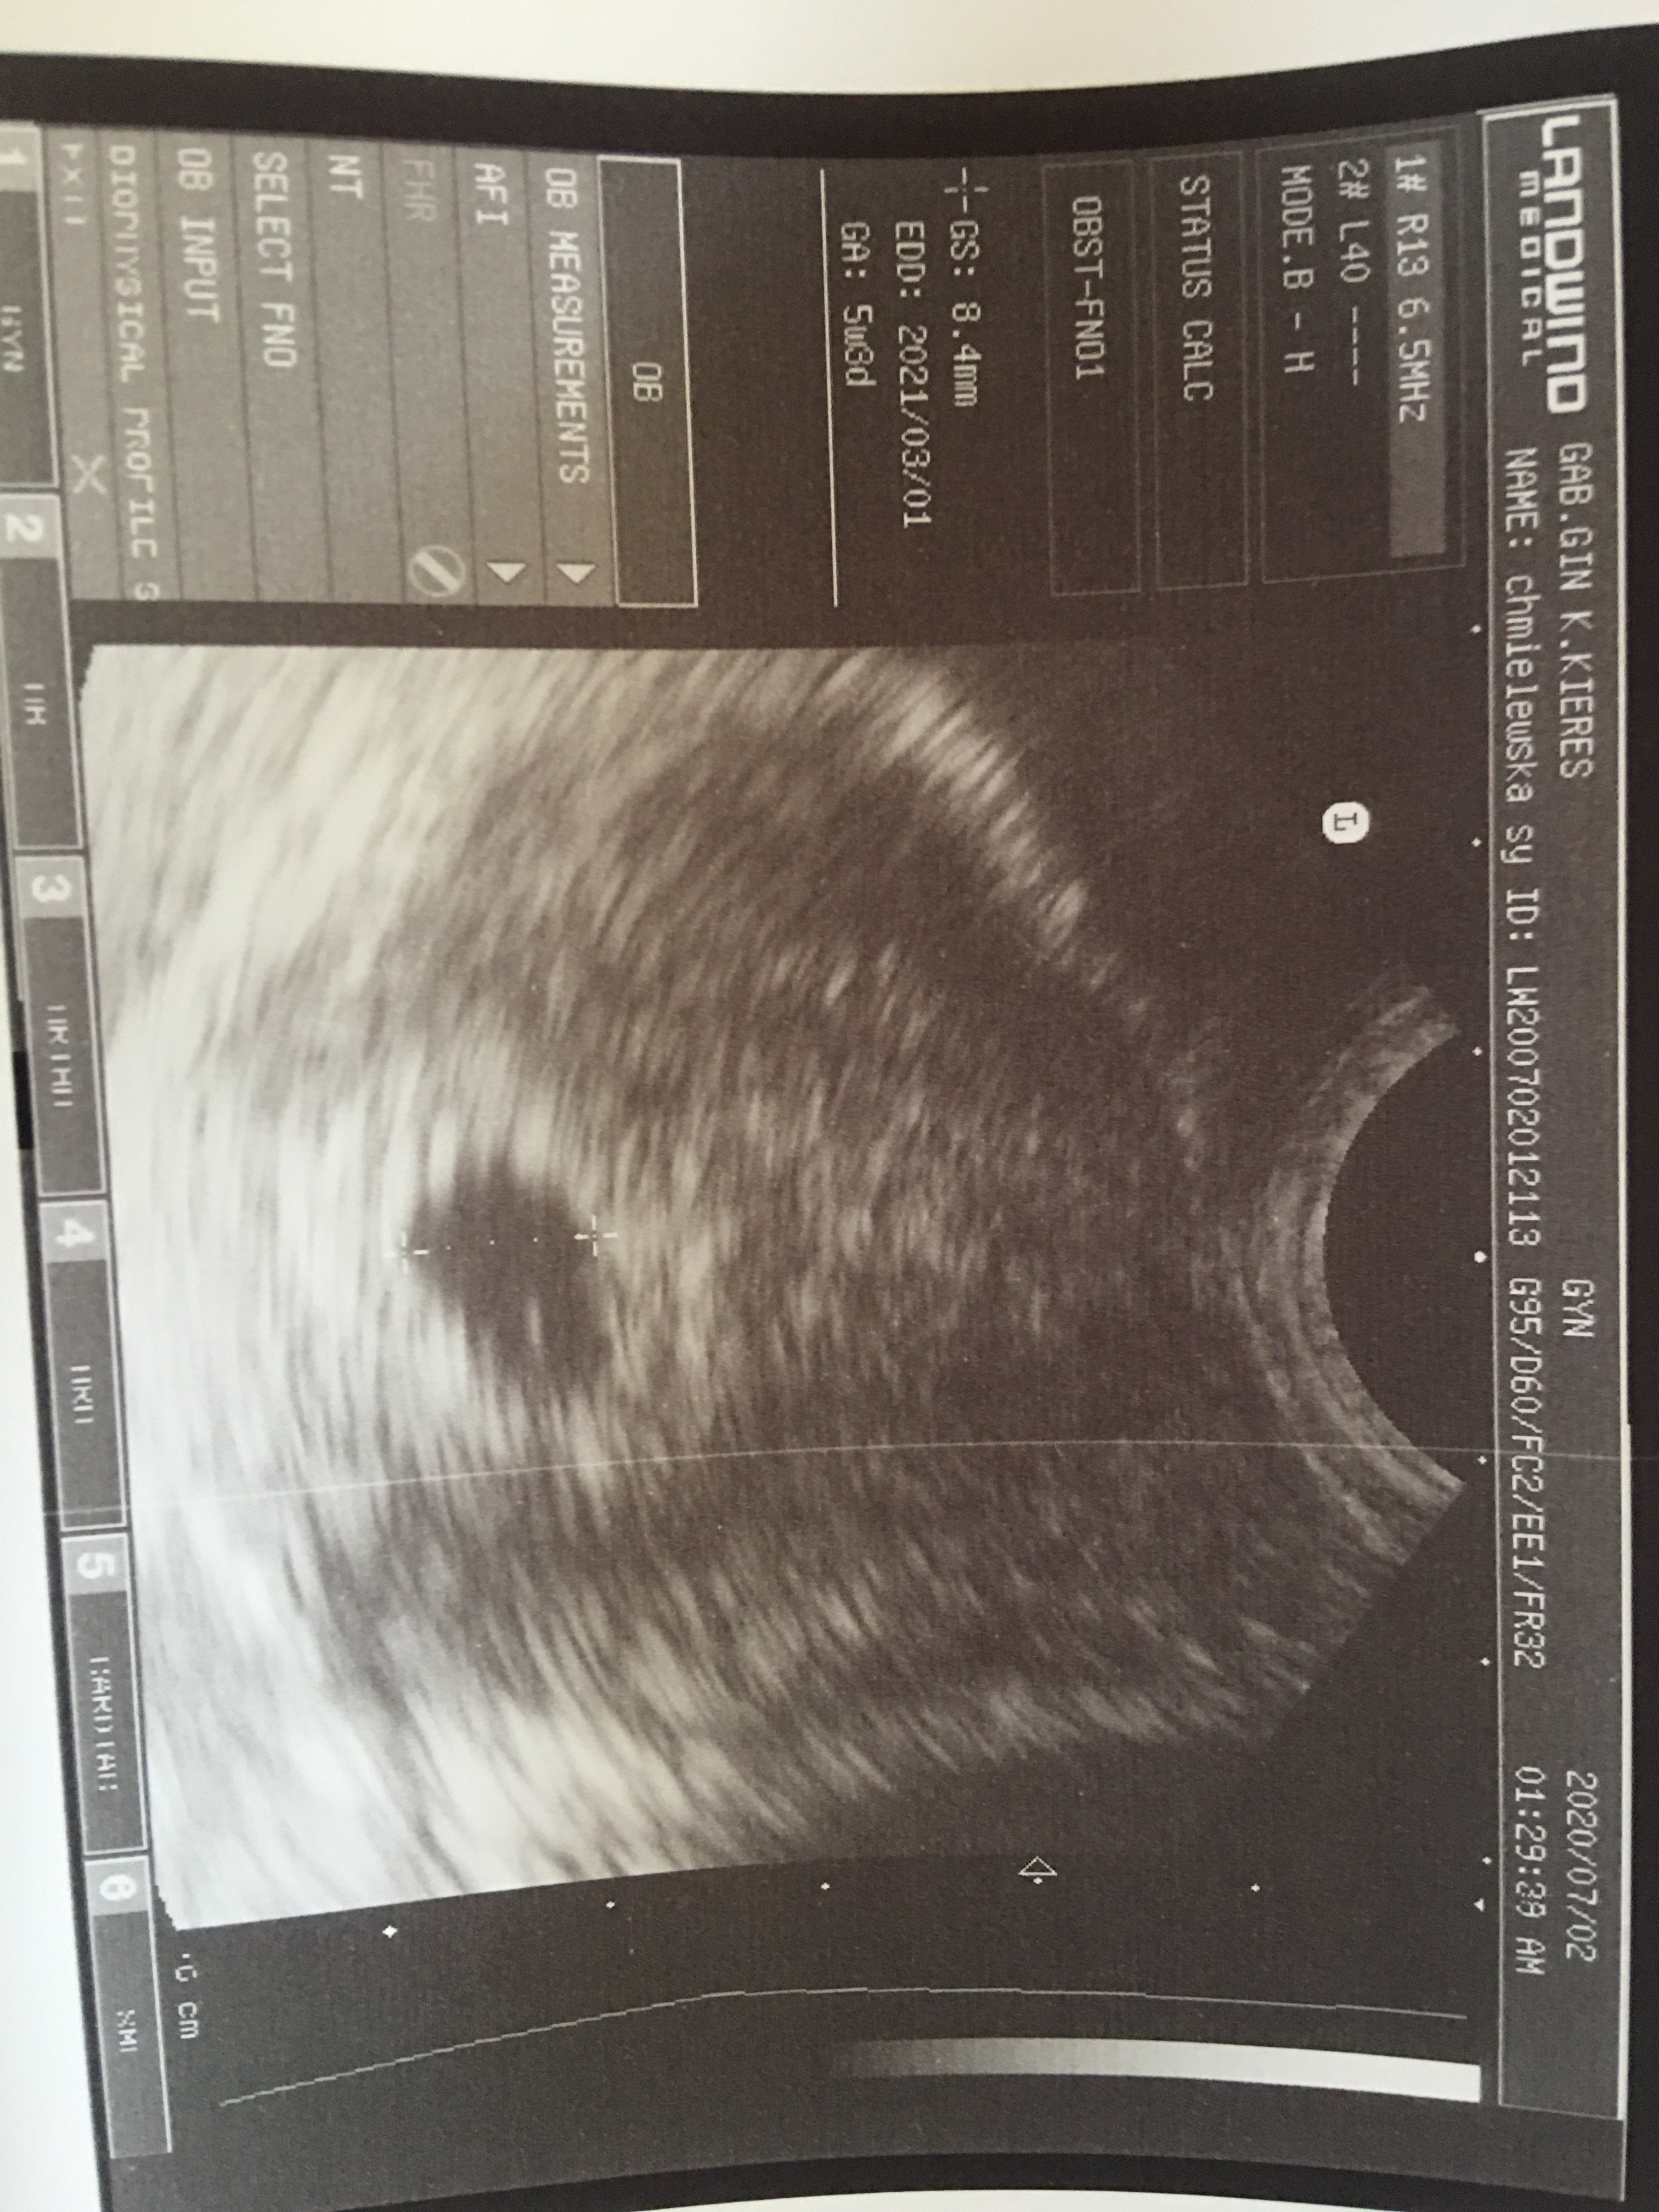

A który to tydzień u Ciebie?? Dobrze że torbiel się zmniejsza, trzymam kciuki. a mdłości to dobry objawWróciłam właśnie z usg. Torbiel się lekko zmiejszył od poniedziałku. Pani doktor sprawdziła pęcherzyk ciążowy widać w nim ciałko żółte zlokalizowane w dobrym miejscu ale zarodka i serduszka jeszcze nie. Nadal mam straszne mdłości i bóle podbrzusza. W poniedziałek kolejna wizyta trzymajcie kciuki Zobacz załącznik 1142381

A to pewnie w poniedziałek będzie już serduszkoZ obliczeń miesiączki to 6 tydzień

5+3tc to też 6tc[emoji4]No tak ale ostatnia miesiączkę miałam 19 maja wiec wychodzi ze 6 ale dzięki dobrze wiedzieć